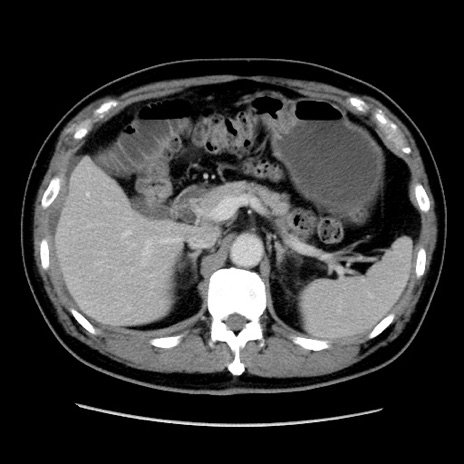

症例16(横断像)

【症例】 70歳代男性

【主訴】 腹痛、嘔吐

【現病歴】 約1ヶ月前より間欠的に腹痛と嘔吐あり、当院消化器内科を受診したところCTで多発する肝臓のLDAを指摘され、精査中であった。以降は消化器症状は安定していたが、2日前より嘔気と腹痛があり、同日より排便・排ガスが消失した。改善認めず、 本日、救急外来を受診した。

【既往歴】 大腸ポリープ切除後。

【身体所見】意識清明・会話良好、BT 36.3℃、BP 127/80mmHg、 P 80bpm、腹部:膨満あり、平坦・軟、上腹部正中および下腹部正中に圧痛あり、反跳痛なし、筋性防御なし。

【データ】WBC 7200、CRP 0.77